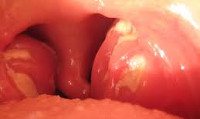

При катаральной ангине у детей осмотр зева выявляет увеличение и гиперемию миндалин, а также небных дужек. Гнойный налет отсутствует; на фоне рыхлого и десквамированного эпителия определяется тонкий слой серозного белесоватого налета. Микроскопически выявляется густая инфильтрация эпителия миндалин лимфоцитами и нейтрофилами.

Признаком фолликулярной ангины у детей служат просвечивающие через эпителиальный покров миндалин гнойные точечные фолликулы величиной до 3 мм («картина звездного неба»). Морфологические изменения в паренхиме миндалин (полнокровие, гиперемия) более выражены; гнойные фолликулы представляют собой лейкоцитарные инфильтраты с явлениями некроза.

Лакунарная ангина у детей протекает с наличием линейного гнойного налета желтоватого цвета, расположенного в лакунах между долями миндалин. Поверхность миндалин ярко гиперемирована и отечна; островки налета в устьях лакун склонны к объединению и образованию широких сливных гнойных очагов. При микроскопическом исследовании обнаруживаются множественные изъязвления эпителия, лейкоцитарная инфильтрация слизистой, гнойное расплавление фолликулов, тромбозы мелких сосудов.

При фибринозной ангине у детей миндалины покрываются пленчатым белесым полупрозрачным налетом. Флегмонозная ангина у детей встречается редко; сопровождается гнойным расплавлением участка миндалины и формированием интратонзиллярного абсцесса (обычно одностороннего).

При гангренозной ангине имеет место язвенно-некротическое изменение эпителия и паренхимы миндалин. При осмотре зева на миндалинах выявляется беловато-серый налет, содержащий в себе большое количество бактерий, лейкоцитов, некротизированную ткань, фибрин. После размягчения и отторжения налета обнажаются язвы с неровными краями. Распространенный некротический процесс может осложниться разрушением, а в дальнейшем – рубцеванием мягкого неба и линии глотки. Некротическая ангина наблюдается при остром лейкозе у детей, дифтерии, скарлатине.

Фарингоскопия у детей определяет разлитую гиперемию миндалин и дужек, инфильтрацию, наличие налета, характер которого позволяет судить о клинической форме ангины. Гнойный налет при ангине легко снимается шпателем, растирается по стеклу и не оставляет кровоточащей поверхности (в отличие от трудноудаляемого налета при дифтерии).